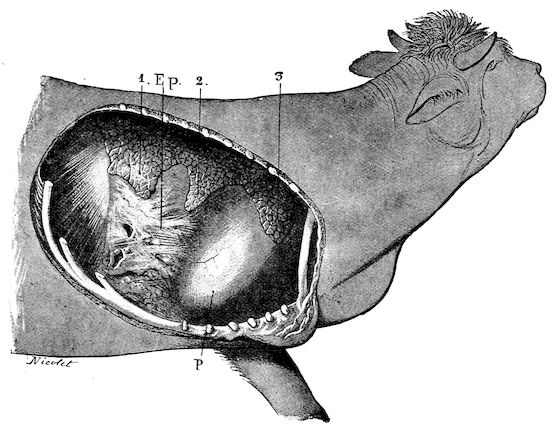

Fig. 8.—Transverse section through the middle region of the face in a pig suffering from osseous cachexia.

18In the final stages, the bones may be cut with a knife, and a time arrives when bony tissue seems completely to have disappeared; thus, as shown in Fig. 8 herewith, it was possible to cut the entire head of a pig into thin slices without the slightest difficulty. All parts of the head had been affected by the softening change.

From the chemical point of view, the diminution in mineral salts and in phosphate of calcium has long been recognised, but the degree of this change varies according to the phase. In human beings the proportions have been estimated as follows: Normal bone, 50 to 80 per cent. of phosphate of calcium; bone in persons suffering from osteomalacia, 5 to 20 per cent. of phosphate of calcium. The changes in the ossein have not been carefully studied. We only know that histologically the ossein becomes fibrillar, and that chemically it no longer retains its normal composition.